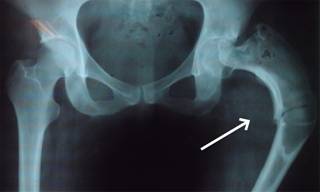

Femenino de 30 años de edad con fractura de cadera izquierda a los 15 años de edad no asociada a evento traumático, el manejo fue conservador y la paciente presentó discrepancia en la longitud de ambas extremidades inferiores por acortamiento del lado afectado. A los 29 años de edad, la paciente se embaraza, durante este tiempo el acortamiento de la extremidad afectada aumentó 5 cm. La radiografía de pelvis mostró deformidad radio-opaca en cabeza femoral izquierda en «cayado de pastor» (Figura 1), datos confirmados por tomografía axial computarizada (Figura 2), por lo que se solicitó valoración por endocrinología manejándola con bifosfonatos y su embarazo concluyó adecuadamente. En el puerperio mediato sufrió caída desde su plano de sustentación, contusión directa en cadera izquierda, dolor, incremento de la deformidad, crepitación ósea y la radiografía simple mostró la deformidad ya mencionada con una fractura subtrocantérica en sitio de displasia, imagen de vidrio despulido, de apariencia quística en cuello femoral, zona trocantérica y subtrocantérica (Figura 3). Ante estos hallazgos se le realizó resección del sitio de lesión y colocación del Sistema Modular de Revisión Femoral ArcosMR (Figura 4). A los 10 meses de la operación la evolución de la paciente era satisfactoria (Figura 5).